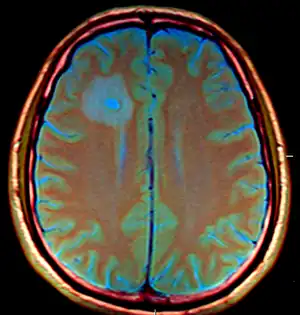

Cranial MRI revealed multiple, contrast-dense masses -abscesses -

The diagnosis of Entamoeba histolytica in the brain abscesses is difficult for several reasons. Firstly, the aerobic and anaerobic cultures generally provide negative results.[9][10] In addition, the CT results are often inconclusive and even the parasitologic stool examinations and abdominal ultrasonography often yield normal results. However, direct examination of the abscess capsule may exhibit necrotic material, foamy histiocytes, rare eosinophills and ingested erythrocytes.[11] Spheric structures may insinuate the presence of Entamoeba histolytica trophozoites with Masson's trichrome stain. Additionally, PCR based analysis of the CSF can be used to positively identify the parasite in the system .[12] Combination of CT scans and PCR based identification along with the serological methods are the current diagnostic measures for detecting Entamoeba histolytica.